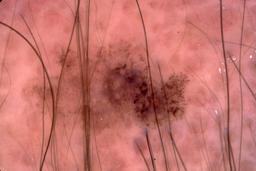

{

"age_approx": 80,

"anatom_site_general": "head/neck",

"concomitant_biopsy": true,

"dermoscopic_type": "contact non-polarized",

"diagnosis_1": "Malignant",

"diagnosis_2": "Malignant melanocytic proliferations (Melanoma)",

"diagnosis_3": "Melanoma Invasive",

"diagnosis_confirm_type": "histopathology",

"image_type": "dermoscopic",

"lesion_id": "IL_0134474",

"melanocytic": true,

"patient_id": "IP_4497472",

"sex": "male"

}